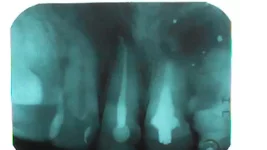

Я назначаю обычно "КТ исследование двух челюстей в прикусе" если необходимо протезирование и сверху и снизу.

Или "КТ исследование одной челюсти" если пациенты планируют протезирование только одного верхнего или нижнего зубного ряда.

Исследование двух челюстей предпочтительнее. Оно более информативно, вот только чуть дороже.

А вот лучевая нагрузка одна и та же. Независимо Вы делаете одну челюсть или две.